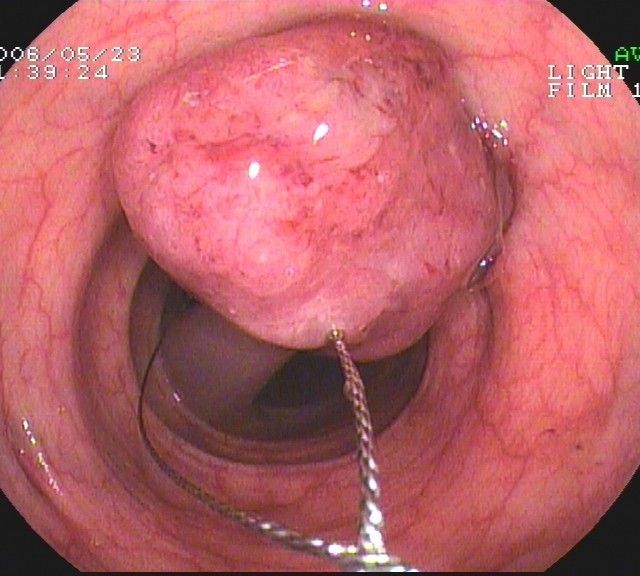

Coloskopie - gestielter hyperplastischer Dickdarmpolyp, mit einer Stromschlinge komplett abgetragen